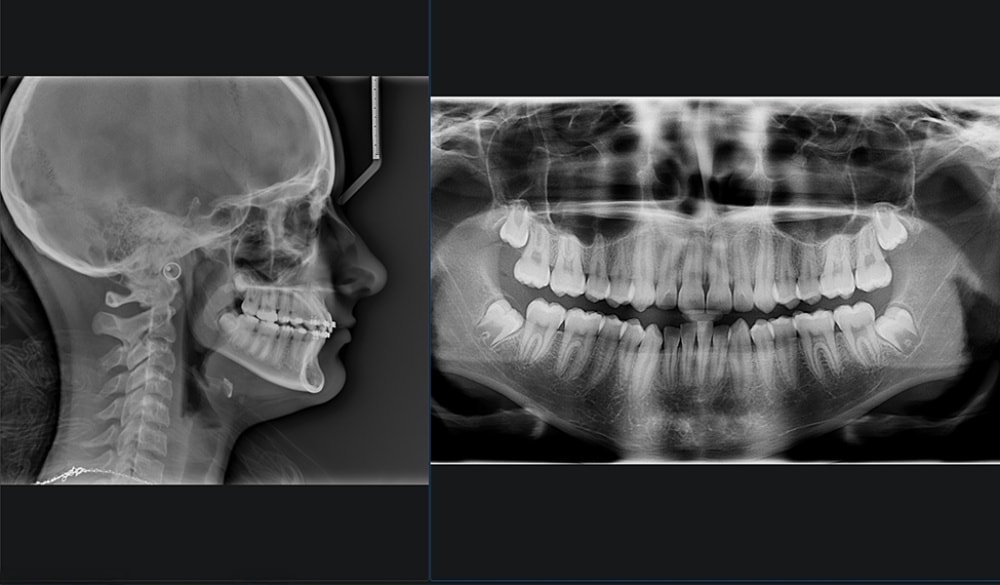

CONEBEAM ou (Scanner)

Le cabinet est équipé d’un appareil de radiographie haute technologie :

un tomographe volumétrique numérique, connu également sous le nom de scanner 3D.

Dans le cas d’un bilan pré-implantaire ou dans le cas de recherche de foyers infectieux, un bilan radiographique 3D est indispensable au docteur Alexandre ORLICK

En une seule prise de cliché 3D, le scanner offre un bilan détaillé.

Il permet de visualiser en 3 dimensions, l’ensemble de votre massif facial particulièrement les maxillaires et les dents.

Il facilite le diagnostic des maladies parodontales, la planification des implants, les interventions chirurgicales de même que les extractions des dents de sagesse. Il permet également la visualisation de kystes.